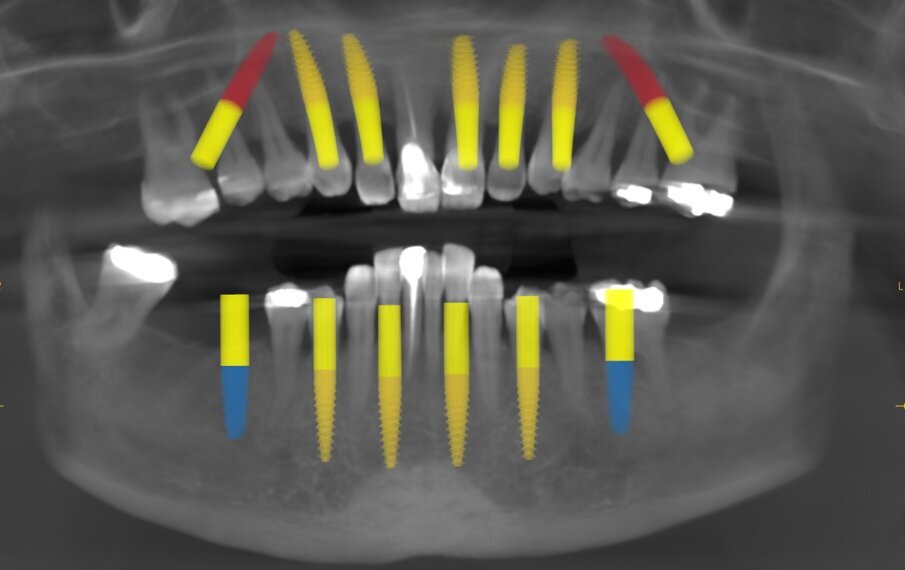

A CBCT scan and panoramic radiograph using the CS 8100 3D device (Carestream Dental; Fig. 3) were taken to accurately capture the information needed to properly plan the treatment for this case that would ensure the most ideal outcome, especially since the patient had discussed how unhappy she was with her existing smile. Using the CS 3D imaging software (Carestream Dental), dental implants were virtually planned in key positions in both arches (Fig. 4).

Fig. 3: Pre-op panoramic radiograph

Fig. 4: Planning with the CS 8100 3D device.

Fig. 16: Post-op panoramic radiograph.

The maxillary provisional restoration was tried in to verify a passive fit over the temporary abutments. Once fit had been confirmed, trimmed dental dam pieces were placed to avoid the restoration (Fig. 11) from locking on during the relining procedure with REBASE III FAST set hard reline material (Tokuyama Dental). After the material had polymerised, the immediate provisional restoration was removed and any access material was removed with the Torque Plus laboratory handpiece (Aseptico) and an acrylic bur (Komet). The same procedures were accomplished in the mandibular arch (Figs. 12–14). Once trimmed and polished, the provisional restorations were seated and tightened with a torque wrench at 15 Ncm (Fig. 15). The access openings were filled in three-quarters of the way with Teflon tape, followed by Cavit filling material (3M ESPE). A postoperative panoramic radiograph was taken immediately after the surgery (Fig. 16).